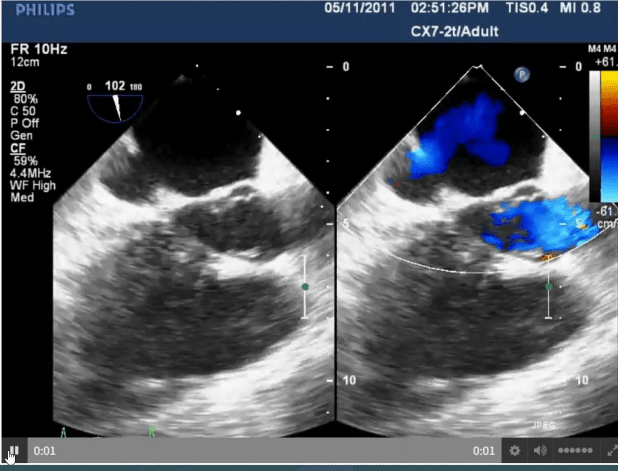

Identify type of ASD

Coronary Sinus ASD